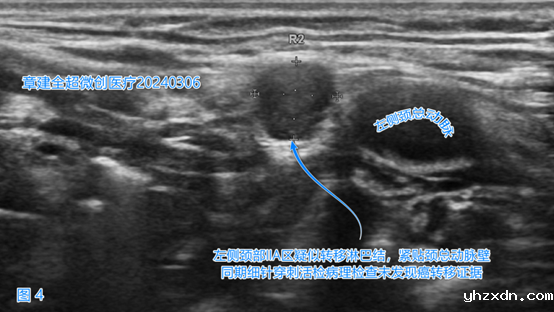

左侧颈部IIA(2A)区(图3)、

右侧颈部VI(6)、右侧颈部VII(7)区(图5)出现了疑似癌转移的淋巴结。